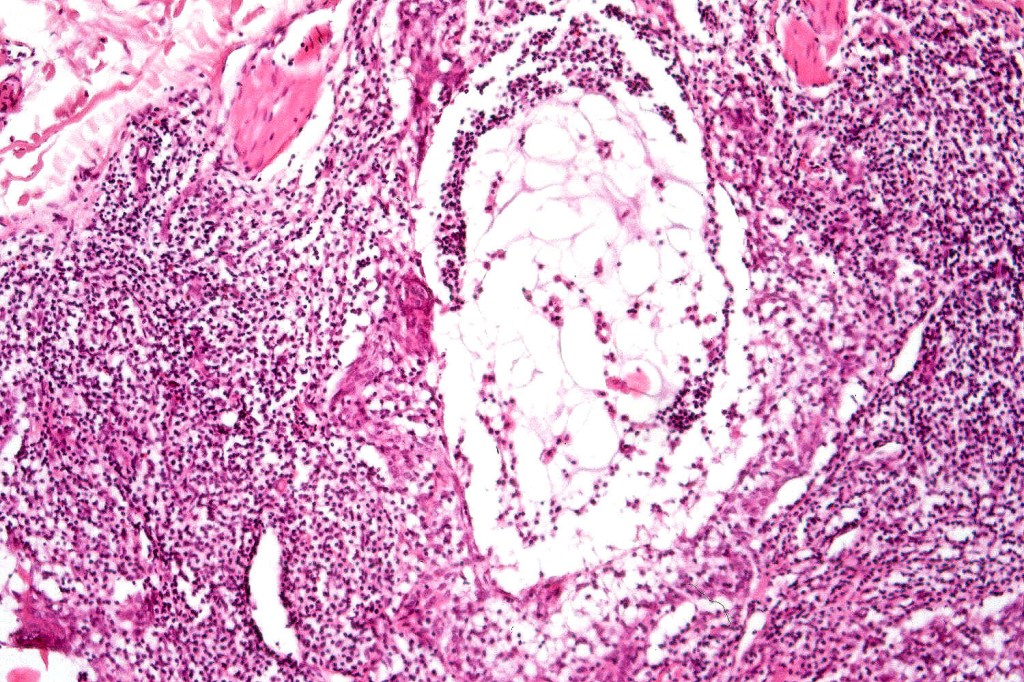

Histological features

•Epidermal involvement often absent

•Follicular infiltration by atypical lymphocytes & Sézary cells

•+/- mucinosis

•+/- basaloid follicular hyperplasia